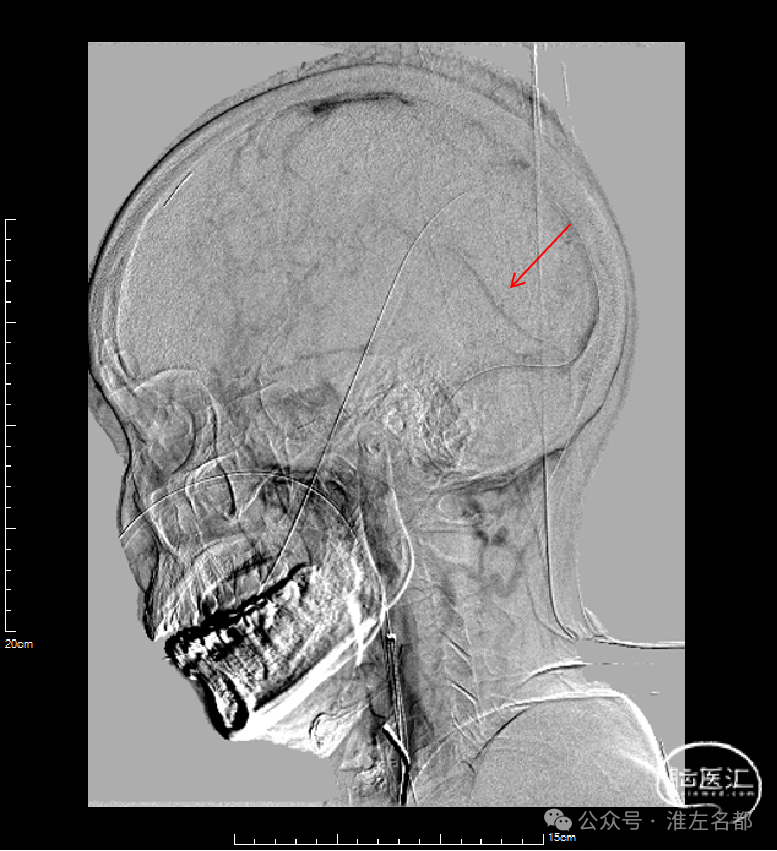

介入治疗后右侧颈动脉造影:上矢状窦、直窦和右侧横窦-乙状窦均见显影,右侧横窦局部狭窄明显。

CTV:上矢状窦、直窦、右侧横窦-乙状窦再通显影,右侧横窦局部管腔狭窄明显。